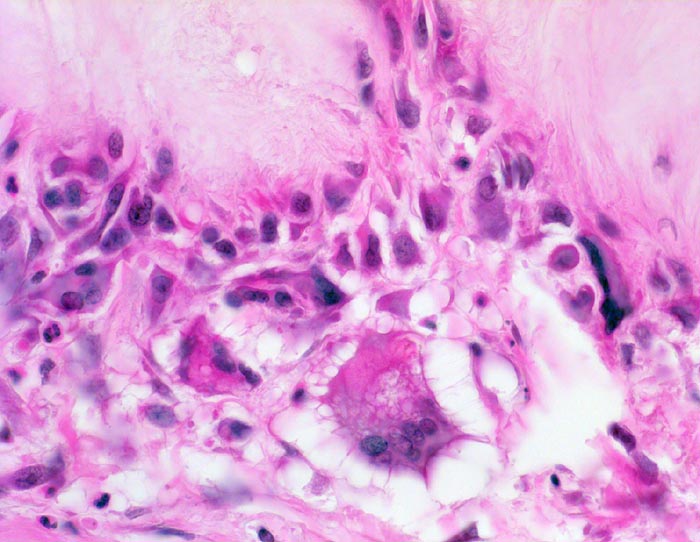

Gichttophus

Systemerkrankung/Immunpathologie

Haut

Die Kristallablagerungen werden von Bindegwebssepten mit Histiozyten, Fremdkörperriesenzellen und Granulozyten umgeben.

Bei teilweise geschlossener Kondensorblende sind Büschel feiner Kristallnadeln erkennbar. Ein Teil der Kristalle ist jedoch oft durch die Gewebspräparation herausgelöst. Natrium-Biurat ist wasserlöslich. Deshalb bei Verdacht auf Gicht Gewebe in absolutem Alkohol, nicht in wässrigem Formalin fixieren und ungefärbte Schnittpräparate polarisationspotisch untersuchen.

Histologie

400